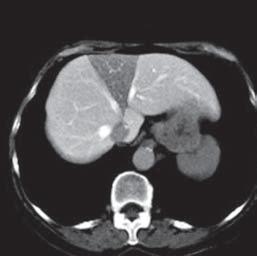

Kazuistika I (segmenty jaterní tkáně)